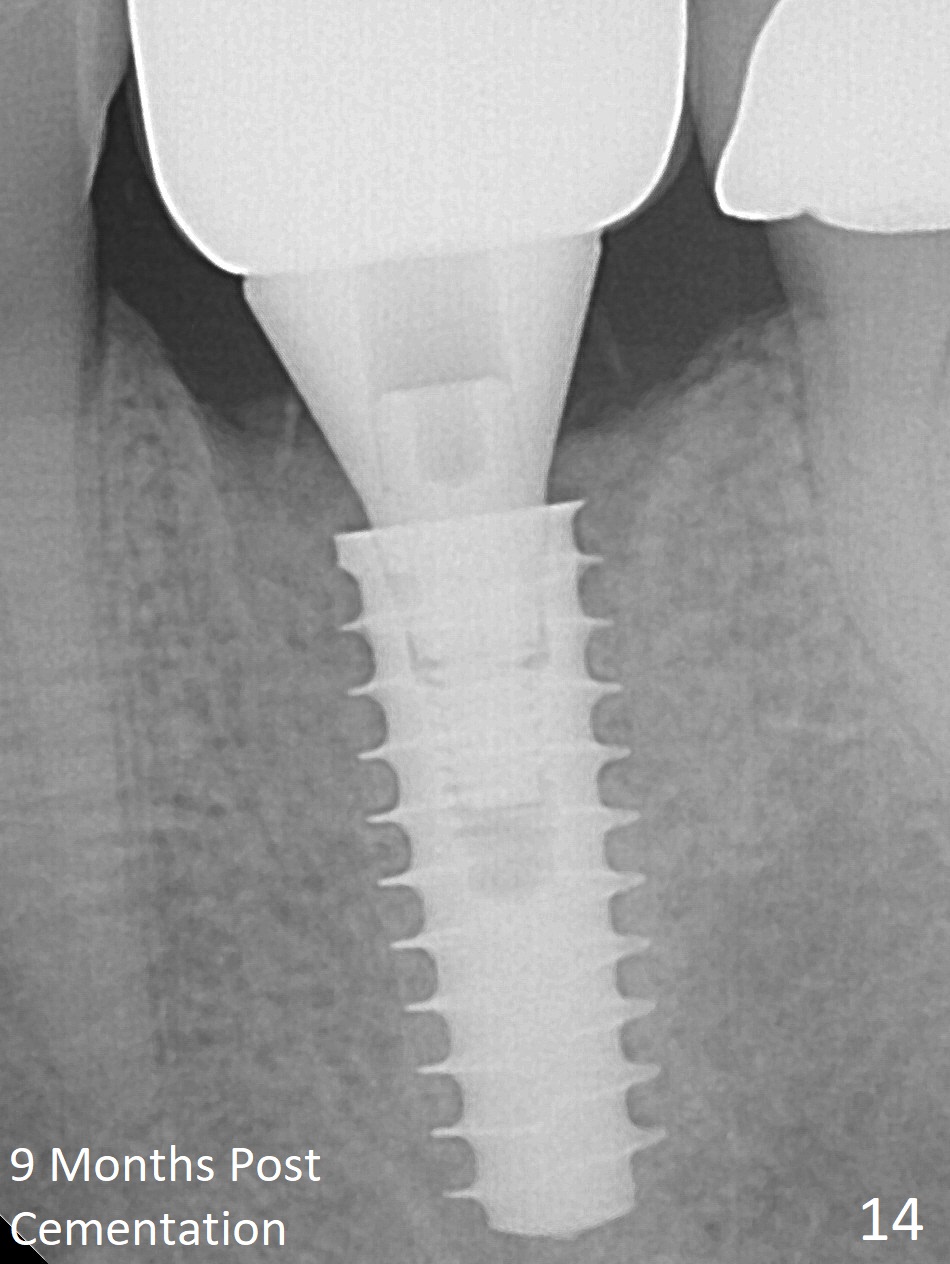

The gingiva looks healthy 8 months postop (3 months post cementation (after abutment screw retightening and addition of porcelain to proximal surfaces, Fig.12).  New bone has apparently covered the implant plateau (Fig.13 arrows). Bone density between threads increases 9 months post cementation (Fig.14).  There is 2 mm bone superior to the implant plateau mesial and distal 1 year 9 months post cementation (Fig.15,16).  The crown/abutment is loose 3 times (3 months (Fig.14), 11 months (between Fig.14 and 15) and 2 years 3 months post cementation).  In spite of being stable 3 years 10 months post cementation, a smaller abutment is placed (Fig.17 (PA), 18 (BW)) with impression for a new crown.  After intraoral cementation, the new crown/abutment is removed for residual cement removal.  When the complex is reseated, it is not smooth, probably due to proximal undercut.  Fortunately the abutment appears to be completely seated, followed by 20 Ncm torque (Fig.19).